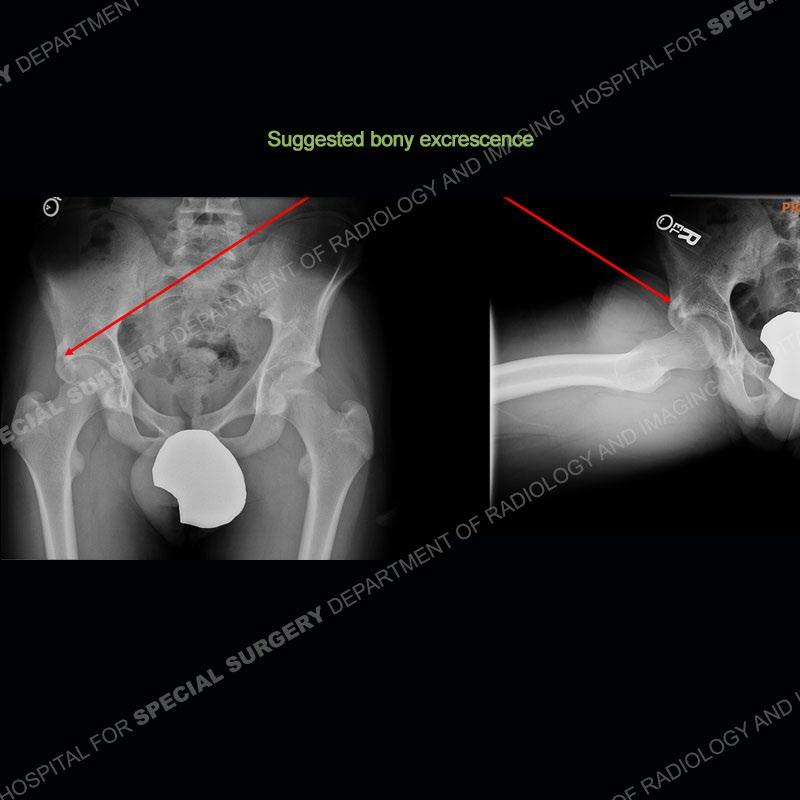

The radiographs demonstrate a suggested bony protuberance or excrescence emanating from the superior aspect of the acetabulum. On the MRI, seen is a large amount of bone about the anterior inferior iliac spine (AIIS) at the level of the origin of the direct head of the rectus femoris. This bone pedunculates inferior to the acetabular rim. No edema pattern is present on the IR sequence and the contralateral left hip acts as a nice internal control where the bony prominence is not present.

The anterior inferior iliac spine is the attachment site of the direct head of the rectus femoris. With avulsion, hematoma and heterotopic ossification may form or in some situations, chronic overuse may precipitate a large enthesophyte. Whatever, the etiology, if bone is present about the AIIS with flexion and internal rotation about the hip, impingement may be precipitated between the bone and the proximal femur. This leads to pain and a limited range of motion.

Prior classification of the ASIS has been performed by Kelly et al. A type I has a smooth wall between the AIIS and the acetabular rim, a type II is when the AIIS extends to the level of the acetabular rim, and a type III is when the AIIS extends distally to the rim. Multiple studies have shown that a type II or type III may be associated with impingement. It is important to always remember that the imaging can only demonstrate findings that may be seen in impingement, but the actual impingement remains a clinical diagnosis.